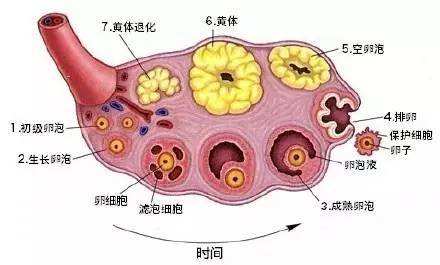

很多女性不孕的一个原因是黄体功能不足,黄体功能不足又称为黄体缺陷,下面介绍下什么是黄体期缺陷以及如何改善。黄体期缺陷有哪些症状?黄体酮水平低月经周期短或不规则大便...

黄体期:月经周期在排卵后,在下一次月经周期的第一天之前发生的部分称为黄体期,黄体期持续10至14天。一些有生育问题的女性的黄体期很短,复发性流产 、 连续两次或多...

患有多囊卵巢综合征女性,在备孕过程中最怕两个问题,一个问题直接导致不孕,另一个问题容易导致流产。到底是哪两个问题呢?第一个问题,排卵障碍导致多囊女性不孕;第二个问...

卵泡发育不好一直是困扰多数备孕夫妻的大难题,一般在月经正常卵泡发育为1.8-2.0CM左右为优势卵泡,卵泡发育不良会影响受孕几率,甚至会不孕。卵子发育不良的女性要...

很多不孕症的患者,在诊治的过程中都经历过一次或数次的药物促排卵。特别是试管婴儿的患者,在一个月经周期内,通过控制性超促排卵和取卵手术,获得了5-20个左右的卵子。...